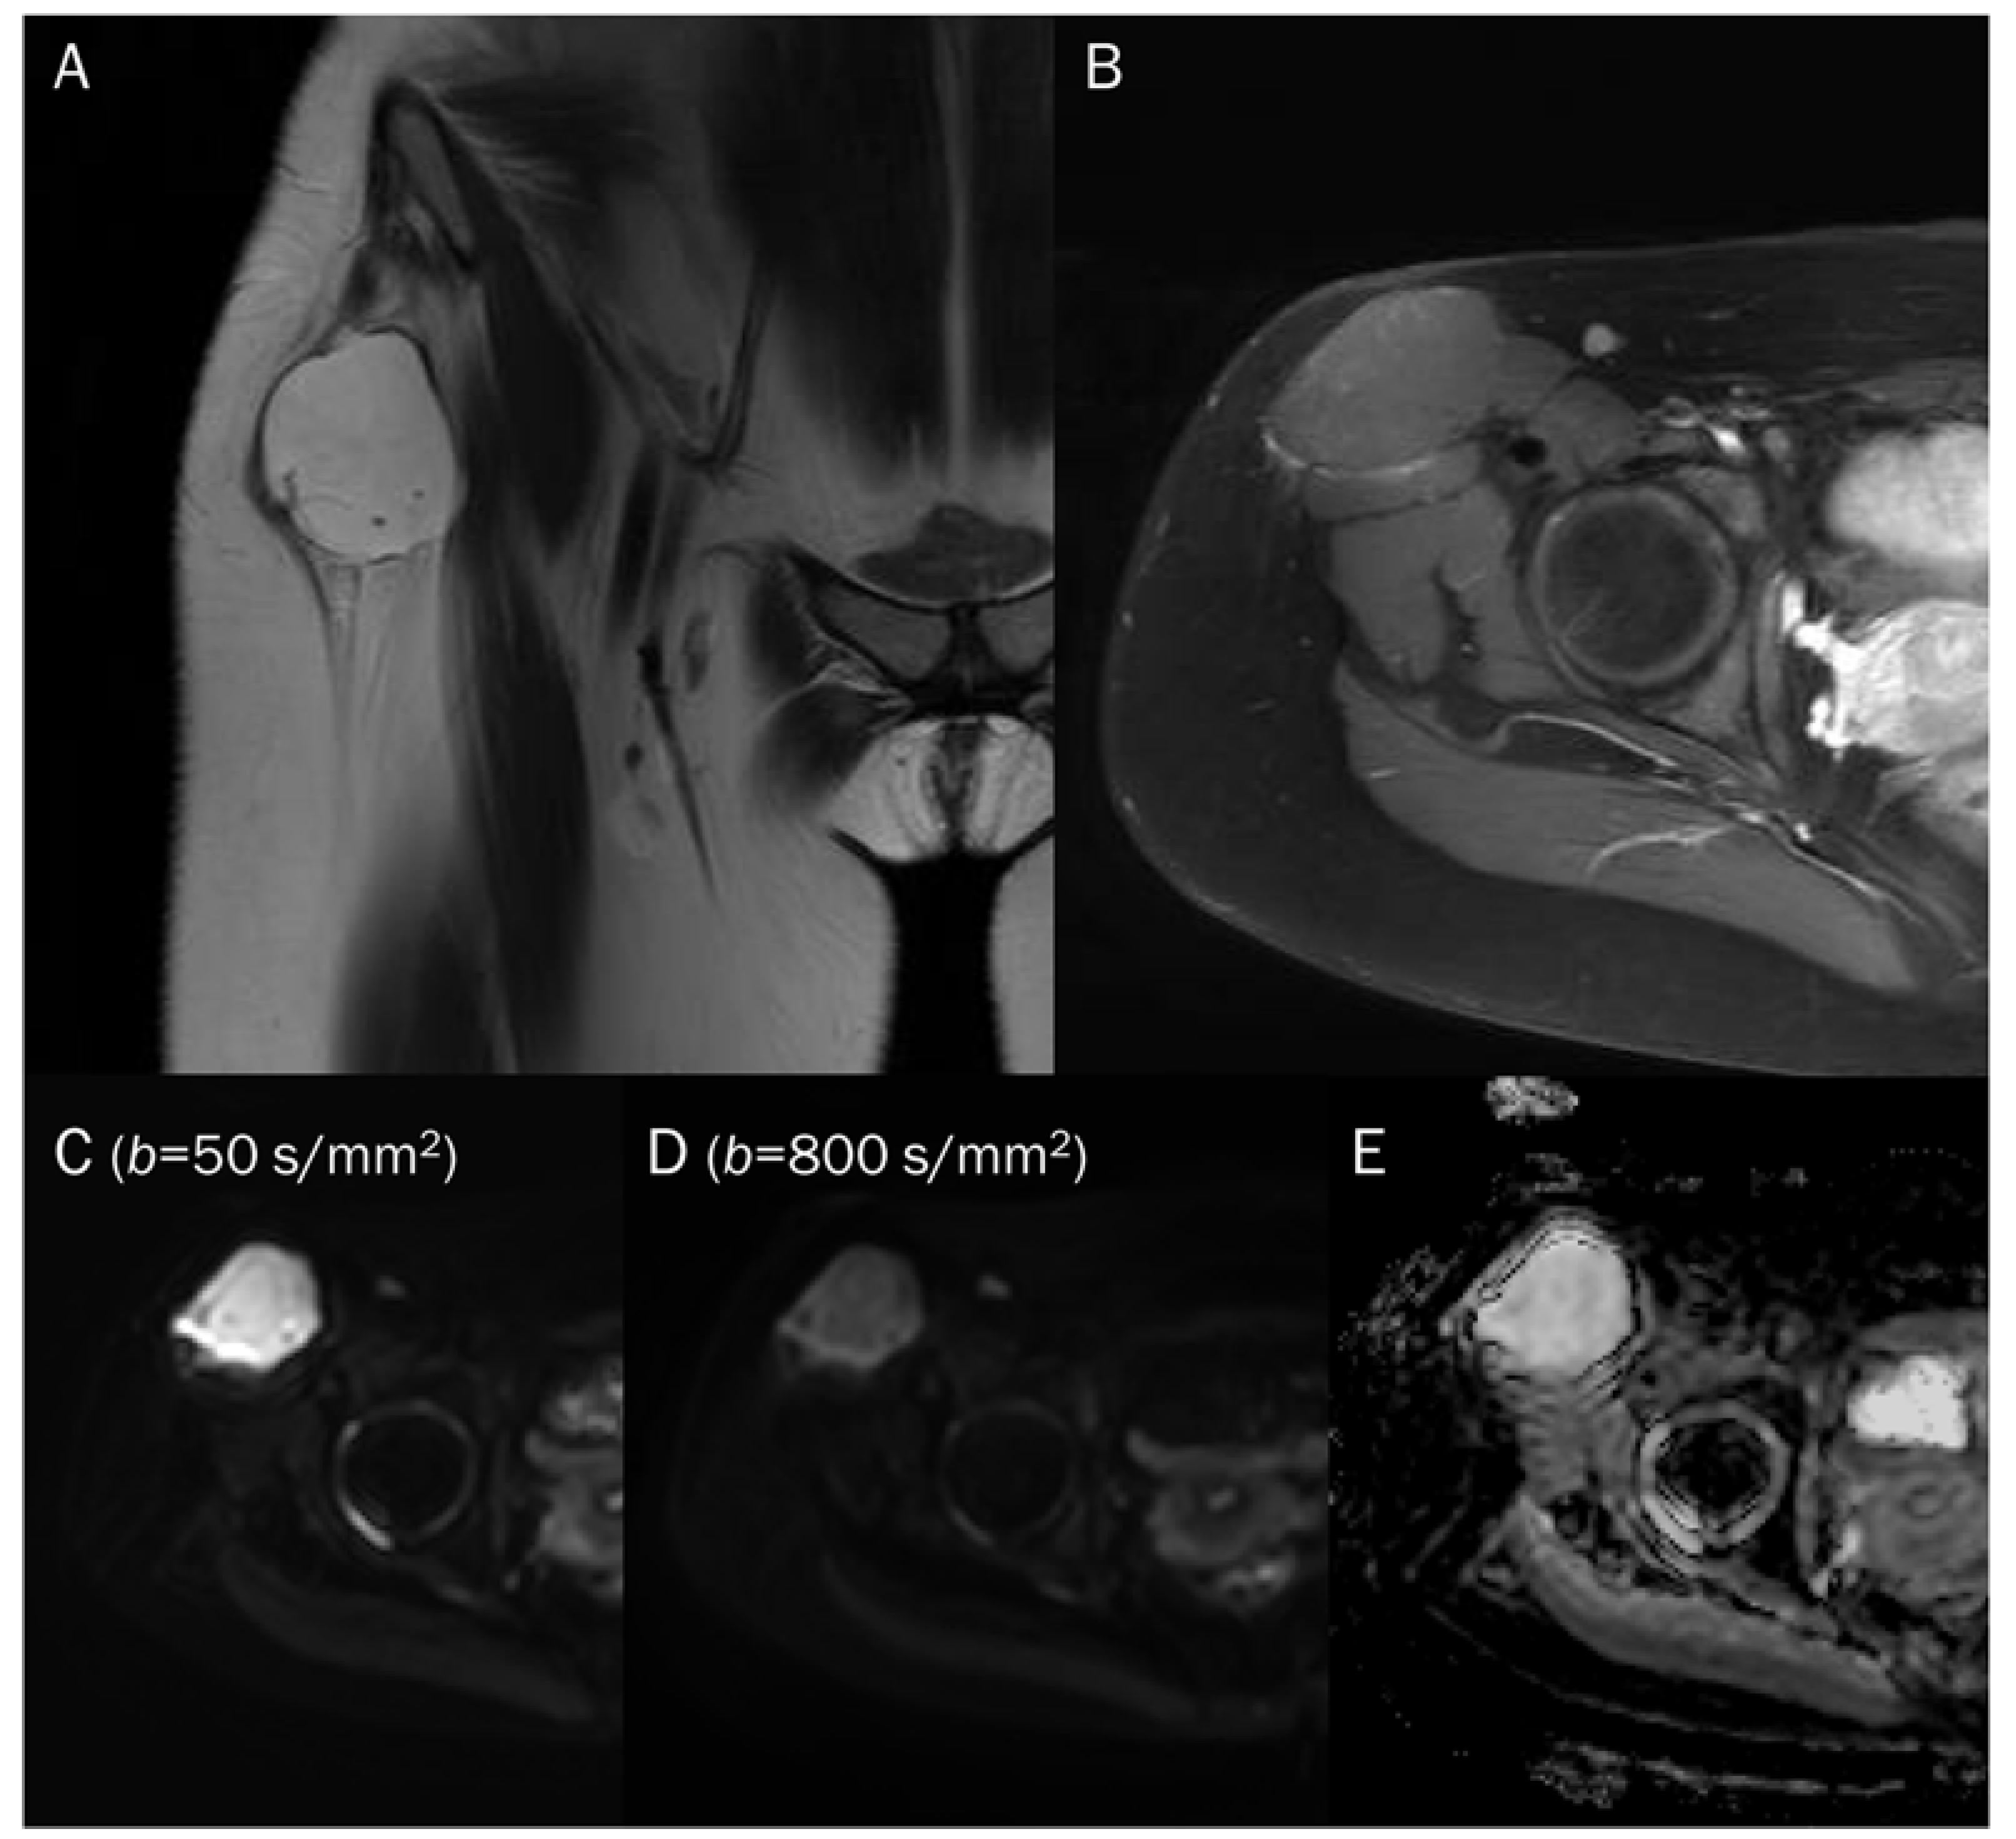

7.1. Cyst